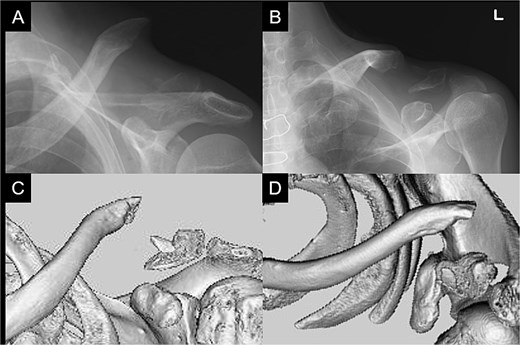

A 66-year-old man presented with left shoulder pain after falling. A Neer Type IIB fracture of the distal clavicle with significant displacement was revealed on radiographs (Fig. 1); however, owing to severe aortic valve stenosis and heart failure, the patient was deemed unfit for surgery. The patient underwent conservative treatment for distal clavicle fracture for 5 months; however, the pain in the left shoulder persisted, and significant skin protrusion caused by a displaced bone fragment was noted. No findings suggestive of neurovascular injury were observed. Radiography and computed tomography (CT) examinations revealed fracture displacement progression (Fig. 2A–C). After undergoing aortic valve replacement 3 months postinjury, the cardiac function of the patient improved and surgery was performed to treat the distal clavicle nonunion.

Radiographs captured immediately after injury show a fracture of the left distal clavicle with displacement.